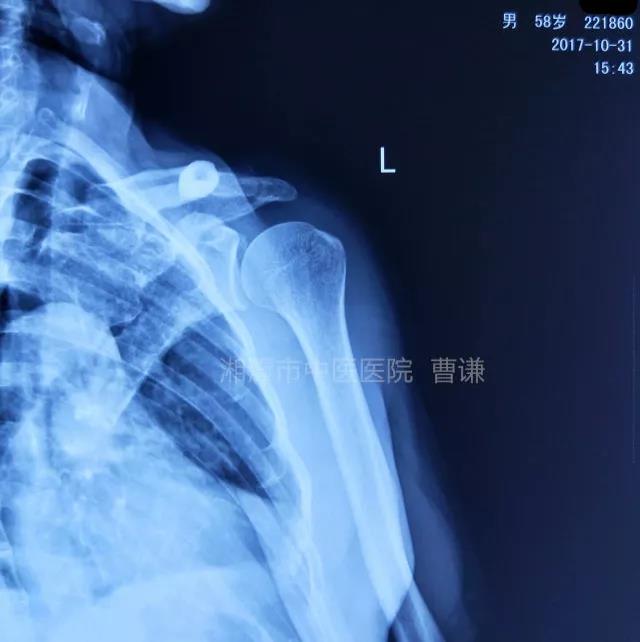

(本病例来自公众号:杨韵琴正骨传承工作室。作者:湘潭市中医院曹谦教授。已获得转载授权)

患者性别:男

患者年龄:58岁

简要病史:骑摩托车跌倒致左肩部肿痛,活动受限,就诊于当地医院,拍片及磁共振检查后诊断为肩袖损伤及肩关节半脱位,予以悬吊固定,因症状缓解不明显就诊于我院。外院拍片情况如下:

应该说是一个典型的“灯泡征”影像,但是并未引起注意。

当地接诊医生应该说还是很负责的,同时拍了健侧片对比:

影像科报告,骨科医生光看报告行吗?

就诊我院后完善CT,诊断明确——左肩关节后脱位:

予以手法复位后拍片复查显示“灯泡征”消失,复位成功。讨论:肩关节后脱位在临床较为少见,特别是影像科经验不足很容易漏报,所以我们临床医生一定要自己仔细阅片,同时要结合体查来进行诊断,防止漏诊。肩关节后脱位时体查也有明显特征:肩关节前方明显变平,喙突较平时明显凸起容易触及,而肩关节后方明显丰满,上臂一般处于内旋内收位,无法主动外旋外展。肩关节后脱位的手法复位相对于前脱位的复位来说也比较容易。患者一般可以取坐位,助手自患侧腋下环抱患者稳定患者躯体,术者一手拉患肢上臂稍牵引内旋,一手自后方推顶肱骨头一般可以复位,如果单纯推顶无法复位也可以术者两手握住伤肢缓慢外展并沿肱骨纵轴牵引,然后逐渐外旋上臂即可复位。整复完成后可以把持患肢作肩关节各个方向的小幅度被动活动,防止肩关节粘连,肩关节后脱位的固定方法与肩关节前脱位的固定方法不同,应将患肢置于上臂外展、后伸、外旋位固定,即外展30度、后伸30度和轻度外旋位,用外展支架固定3周后,循序渐进开始肩关节功能康复。